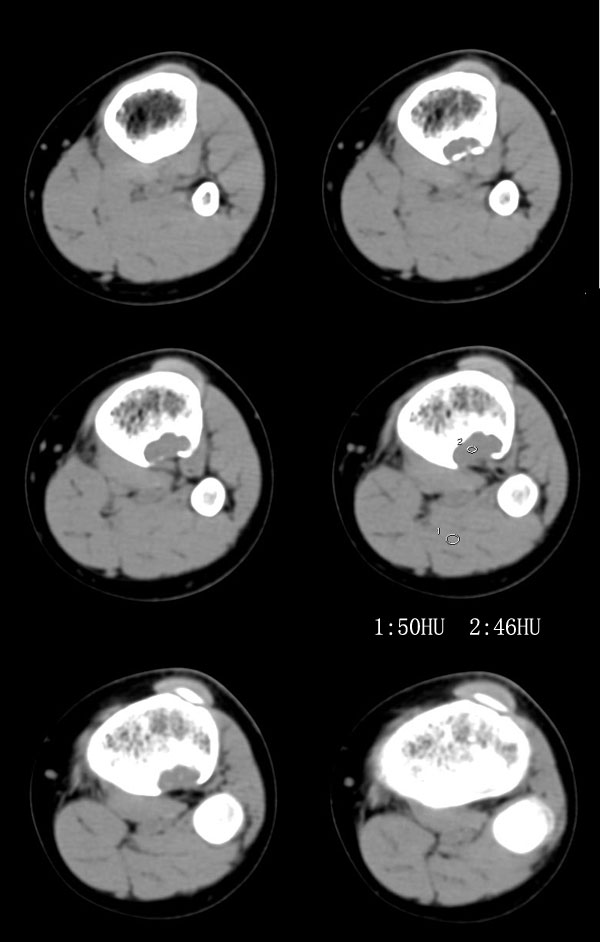

以下是引用37度在2010-1-7 12:22:00的发言:[br]左胫骨上段纤维性骨皮质缺损(非骨化性纤维瘤).

以下是引用dyqct在2010-1-7 14:54:00的发言:[br]考虑为左胫骨上段纤维性骨皮质缺损 ,可自愈.

以下是引用xkncyyhyq在2010-1-7 9:54:00的发言:[br]考虑为纤维性骨皮质缺损